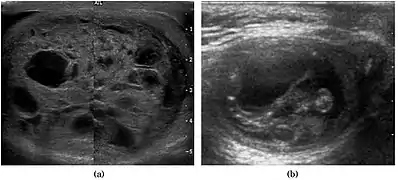

Teratoma Although teratoma is the second most common testicular tumor in children, it affects all age groups. Mature teratoma in children is often benign, but teratoma in adults, regardless of age, should be considered malignant. Teratomas are composed of all three germ cell layers, i.e. endoderm, mesoderm and ectoderm. At ultrasound, teratomas generally form well-circumscribed complex masses. Echogenic foci representing calcification, cartilage, immature bone and fibrosis are commonly seen [Fig. 5]. Cysts are also a common feature and depending on the contents of the cysts i.e. serous, mucoid or keratinous fluid, it may present as anechoic or complex structure [Fig. 6].

Fig. 5. Teratoma. A plaque-like calcification with acoustic shadow is seen in the testis.

Fig. 6. Mature cystic teratoma. (a) Composite Image. Mature cystic teratoma in a 29-year-old man. Longitudinal sonography image of the right testis shows a multilocular cystic mass. (b) Mature cystic teratoma in a 6-year-old boy. Longitudinal sonography of the right testis shows a cystic mass containing calcification with no obvious acoustic shadow.